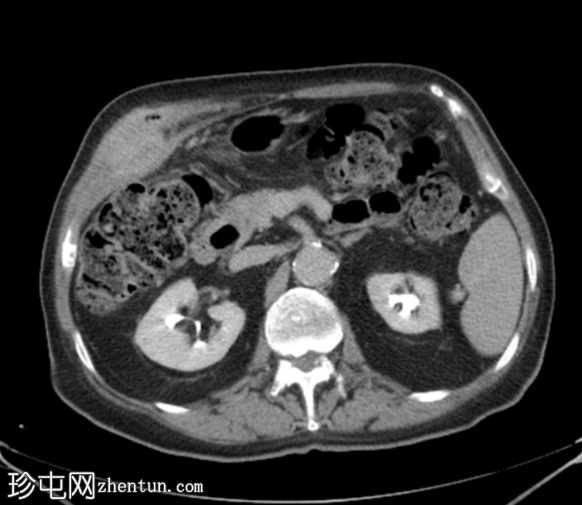

CT

轴位

平扫

胆囊底部可见一枚较大的(3厘米)高密度结石,胆囊壁增厚并强化,主要位于胆囊底部。胆囊壁可见一小穿孔,感染扩散至胆囊外,并在肝下区可见气体腔。感染进一步扩散至腹壁肌肉,腹壁肌肉内可见脓肿,边缘强化明显,囊性坏死中心,腔内可见气体腔。十二指肠第一段与炎症胆囊粘连。

检查结果提示急性胆囊炎合并腹壁脓肿。